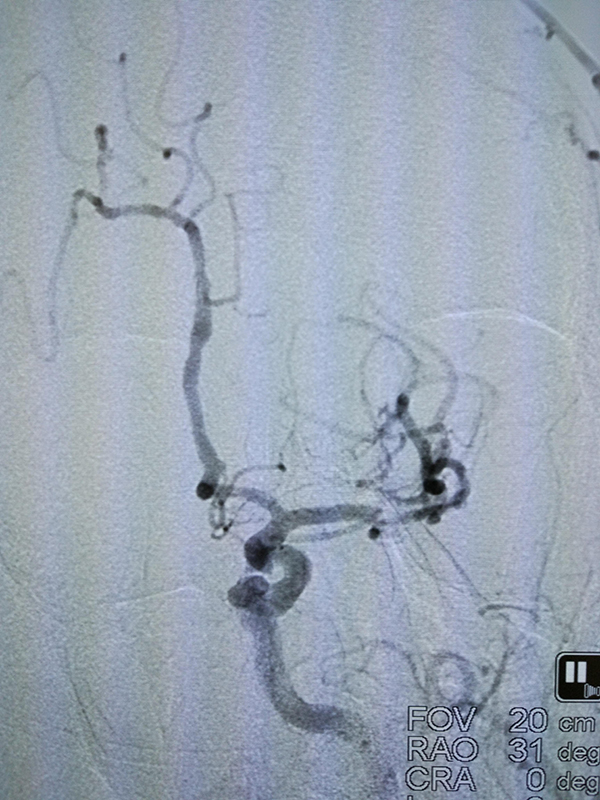

术前

术后

前日凌晨5点,宋先生在起床上厕所时突然发现右侧肢体乏力,不能行走,伴随说话不清、大便失禁,家属得知后立即将其送至省人民捷克论坛 马王堆院区急救。捷克论坛 卒中中心立即接诊了该患者,并启动了卒中绿色通道。经检查发现,宋先生为急性脑梗死高危患者,有急诊全脑血管造影术指征。抽血、CT、术前用药、术前准备、麻醉……卒中绿色通道的每一个部门围绕着宋先生有条不紊的进行。入院1小时内,患者在全麻下进行了全脑血管造影术。通过造影显示,患者左侧大脑中动脉M1段重度狭窄并形成血栓,如不及时处理,患者将有生命危险。周文胜主任带领着卒中中心医护人员立即对患者实施了脑血管内支架植入取栓术和支架植入术。手术顺利完成,术后患者神志清楚,说话流利,四肢活动接近正常。目前,宋先生正在进一步的康复治疗中。